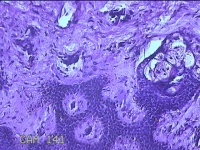

性别

男

年龄

23岁

临床诊断

右耳部肿物

一般病史

右耳前无痛性肿物20余年。

标本名称

大体所见

灰白暗红色肿物0.7x1.5x0.2cm一个,表面糜烂。

组织没固定好